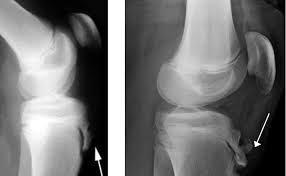

Para confirmar la sospecha y descartar fracturas traumáticas agudas, la radiografía simple en proyecciones anteroposterior y lateral constituye la primera línea de imagen, revelando típicamente fragmentación y esclerosis de la apófisis. En estadios muy tempranos, la ecografía de alta resolución es superior para detectar el engrosamiento del tendón y la bursitis infrapatelar, mientras que la resonancia magnética se reserva para casos refractarios que superan los tres meses de evolución, permitiendo visualizar con precisión el edema de médula ósea.